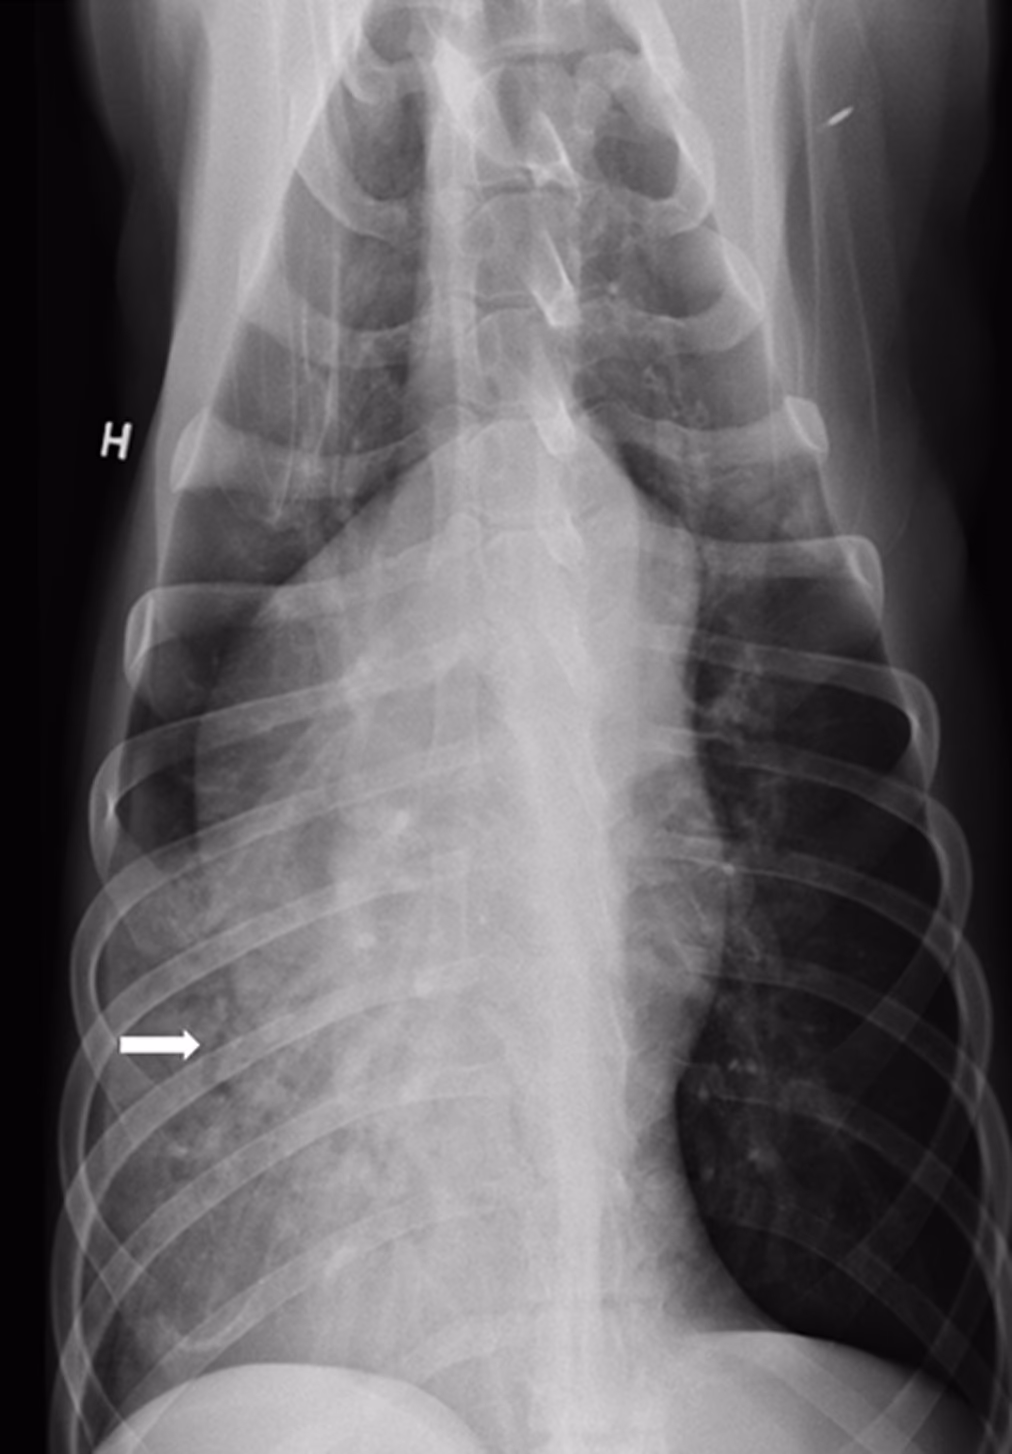

Svaret er ja, selvom det er en sjældenhed. Zoonotisk transmission, altså smitte fra dyr til menneske, er dokumenteret. Et konkret patienttilfælde illustrerer tydeligt, hvordan en sådan infektion kan forløbe. En patient, som havde tæt kontakt med en hest, der formodes at være død af kværke, udviklede symptomer på tidlig sepsis (blodforgiftning) få dage senere. I første omgang mistænkte lægerne komplikationer fra en nylig medicinsk procedure, men en CT-scanning afslørede tegn på lungebetændelse. Efterfølgende blodprøver bekræftede en bakteriæmi – tilstedeværelsen af bakterier i blodet – med den sjældne humane patogen, S. equi.

Det formodes, at patienten oprindeligt udviklede en subklinisk lungebetændelse efter at have været udsat for den syge hest. Infektionen forblev måske i lungerne uden at give markante symptomer, indtil en efterfølgende medicinsk procedure potentielt gav bakterien adgang til blodbanen, hvilket førte til en livstruende tilstand. Dette tilfælde understreger, at selvom de fleste humane infektioner med S. equi manifesterer sig som meningitis (hjernehindebetændelse), er lungebetændelse en reel og alvorlig mulighed. Uden hurtig diagnose og behandling kunne en sådan infektion have været dødelig.

At diagnosticere en S. equi infektion hos et menneske kræver en høj grad af mistanke, især på grund af sygdommens sjældenhed. En detaljeret anamnese, hvor der spørges ind til dyrekontakt (en zoonotisk historie), er altafgørende. Diagnosen bekræftes typisk ved at dyrke bakterien fra blodprøver, spinalvæske (ved mistanke om meningitis) eller vævsprøver. Billeddiagnostik som CT-scanninger kan visualisere omfanget af infektionen, f.eks. i lungerne eller hjernen.